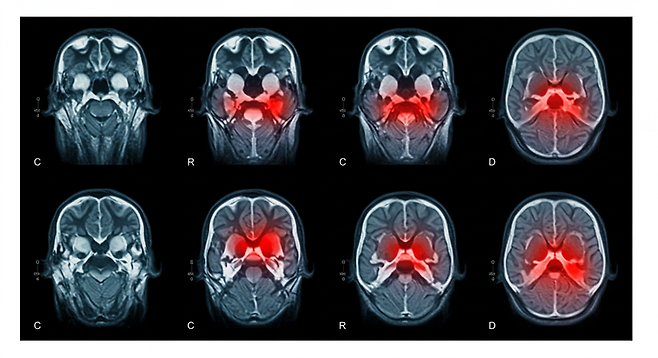

뇌경색, 왜 조기 발견이 중요할까?

뇌경색은 뇌혈관이 막혀 뇌조직이 손상되는 질환으로, 발생 후 3-4.5시간 이내에 치료받아야 후유증을 최소화할 수 있습니다. 하지만 많은 사람들이 초기 증상을 단순한 피로나 스트레스로 오해해 치료 시기를 놓치고 있습니다.